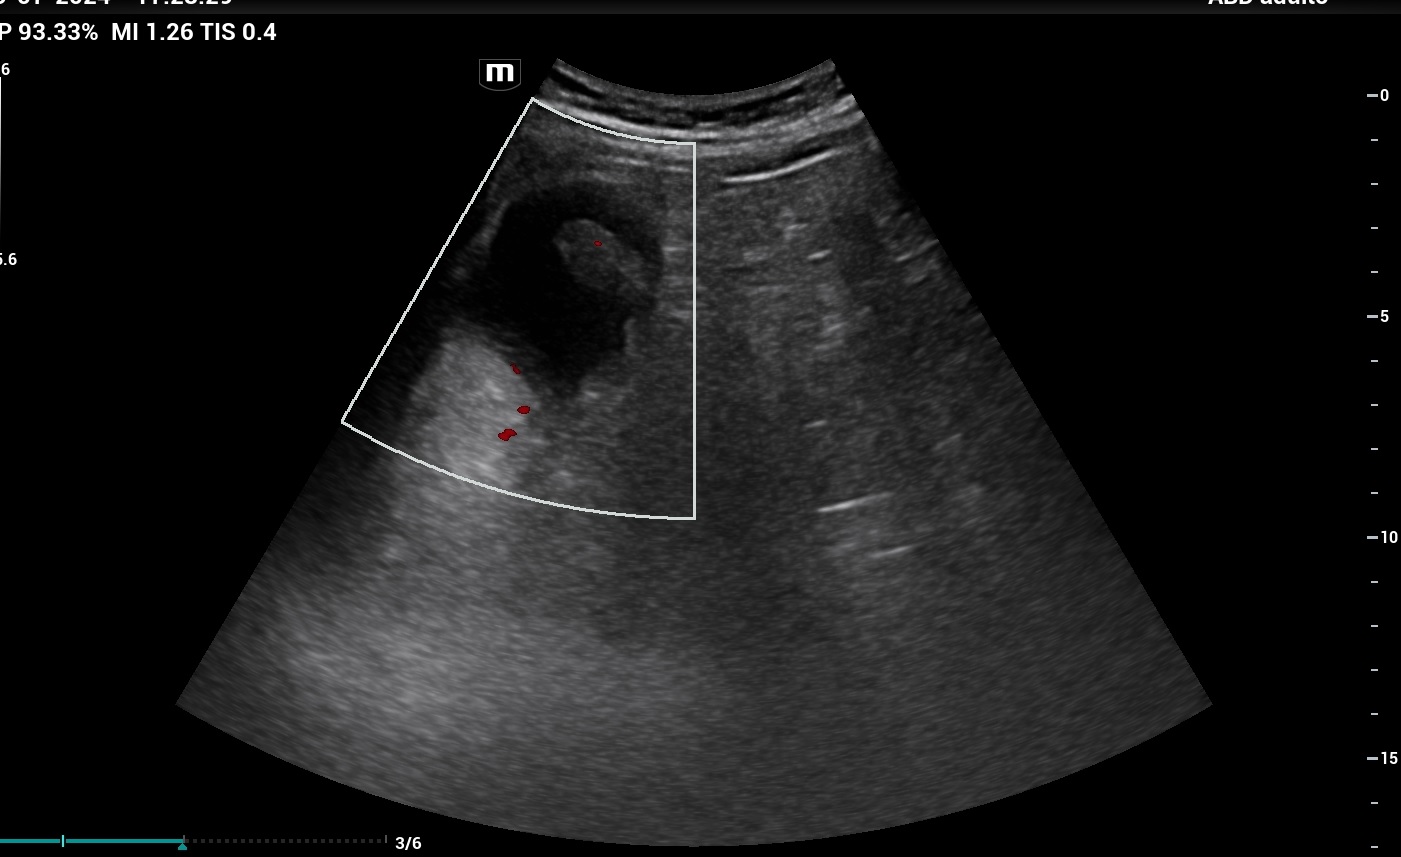

En la ecografía clínica, la vesícula biliar presentaba imagen ecogénica de bordes bien definidos, sin sombra acústica posterior, localizada en cúpula vesicular. Se pidió al paciente que se colocara en decúbito lateral izquierdo y se comprobó que la lesión continuaba localizada en cúpula vesicular, sin haberse desplazado al movilizar al paciente. Dicha lesión presentaba un tamaño de 2,8 x 1,7 cm (imagen 28), y se activó Doppler, observándose que dicha lesión tenía una captación central de Doppler, correspondiente a un vaso nutricio. La pared de la vesícula no estaba engrosada y no había dilatación de vía biliar intra ni extrahepática.

El diagnóstico fue de pólipo vesicular. Dentro del diagnóstico diferencial tenemos que pensar en un cólico biliar, una colecistitis, una coledocolitiasis o una colangitis. En pacientes con episodios repetidos de dolor en hipocondrio derecho, con la ecografía podemos descartar que se trate de colelitiasis al observar cálculos en su interior. Si el paciente asocia fiebre, la ecografía nos ayudará con el diagnóstico de colecistitis (presencia de colelitiasis, vesícula distendida, y pared engrosada). Como en este caso, podemos encontrar patología menos prevalente y que se diferencia de las litiasis por no presentar sombra acústica posterior, por no ser móviles y porque en ocasiones pueden presentar captación Doppler.

En la ecografía abdominal reglada se confirmó que se trataba de un pólipo vesicular sospechoso de adenoma, y se derivó a las consultas de Cirugía General y Digestivo.